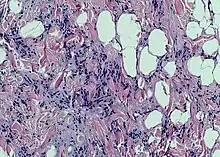

Spindle cell lipoma

Spindle cell lipoma is an asymptomatic, slow-growing subcutaneous tumor that has a predilection for the posterior back, neck, and shoulders of older men.[1]:625[2]